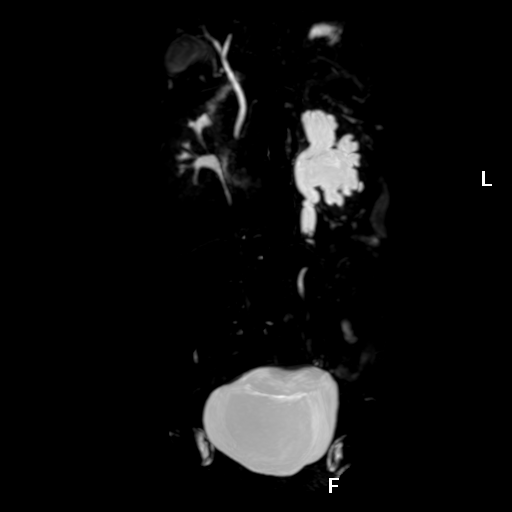

磁共振泌尿系水成像技术(MRU)是一种无创性尿路检查方法,利用尿液中的水作天然对比剂达到“造影的目的,通过重T2加权成像技术,可突出显示尿路中的水的信号,抑制周围组织信号,然后将得到的原始图像进行后处理技术得到MRU图像,其对尿路梗阻以上尿路积水显示很清晰,亦可显示梗阻部位所在及其形态与大小;对输尿管狭窄或结石的显示,可根据梗阻部位的形态加以判断。